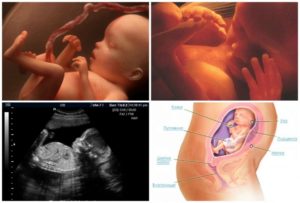

Как же выглядит плод на фото УЗИ на 23-ей акушерской неделе беременности:

- Малыш выглядит еще красненьким и сморщенным, но подкожный жир уже начинает активно формироваться, а кожа потихоньку будет разглаживаться.

- Эмбрион начинает познавать среду вокруг себя, испытывать тактильные ощущения, а поэтому хватает ручками за свое тело, ножки, пуповину, сует пальчик в ротик.

- Пищеварительная система плода уже практически сформирована. Малыш сейчас заглатывает в сутки почти поллитра амниотической жидкости, которая выводится из его организма в виде мочи. Питательные вещества накапливаются в кишечнике в виде мекония – первородного кала, который выйдет практически сразу после рождения.

- Головной мозг плода уже активно функционирует, как и ЦНС. Многие ученые предполагают, что уже сейчас ваш ребенок способен видеть сны.

- Эмбрион уже способен открывать глазки, различает день и ночь, а кроме того, реагирует на звуки.

УЗИ на 23 неделе беременности

Ультразвуковое исследование на 23 акушерской неделе беременности не назначается. УЗИ проводится в тех случаях, когда есть осложнения или какие-либо риски в течение беременности и развитии плода.

Тогда врач-узист определит соответствие физических параметров эмбриона его биологическому возрасту, проверит состояние плаценты и оценит сердцебиение плода. Нормой является 180-190 ударов в минуту.

Узи на 23-й неделе беременности

23 неделя беременности – идеальное время для УЗИ, ведь в этот период определить пол будущего ребенка не составит никакого труда. Безусловно, основной задачей ультразвукового исследования является определение состояния малыша.

В процессе ультразвукового исследования врач должен определить размеры ребенка, провести осмотр внутренних органов ребенка и соотнести полученные показания с текущим сроком беременности. Всё это необходимо для исключения наличия патологий. Кроме того, специалист должен оценить размеры матки, а также состояние плаценты и почек.

При желании, будущая мама во время УЗИ может попросить сделать фото малыша. Снимок с 23 недели беременности станет прекрасным началом личного альбома вашего малыша.